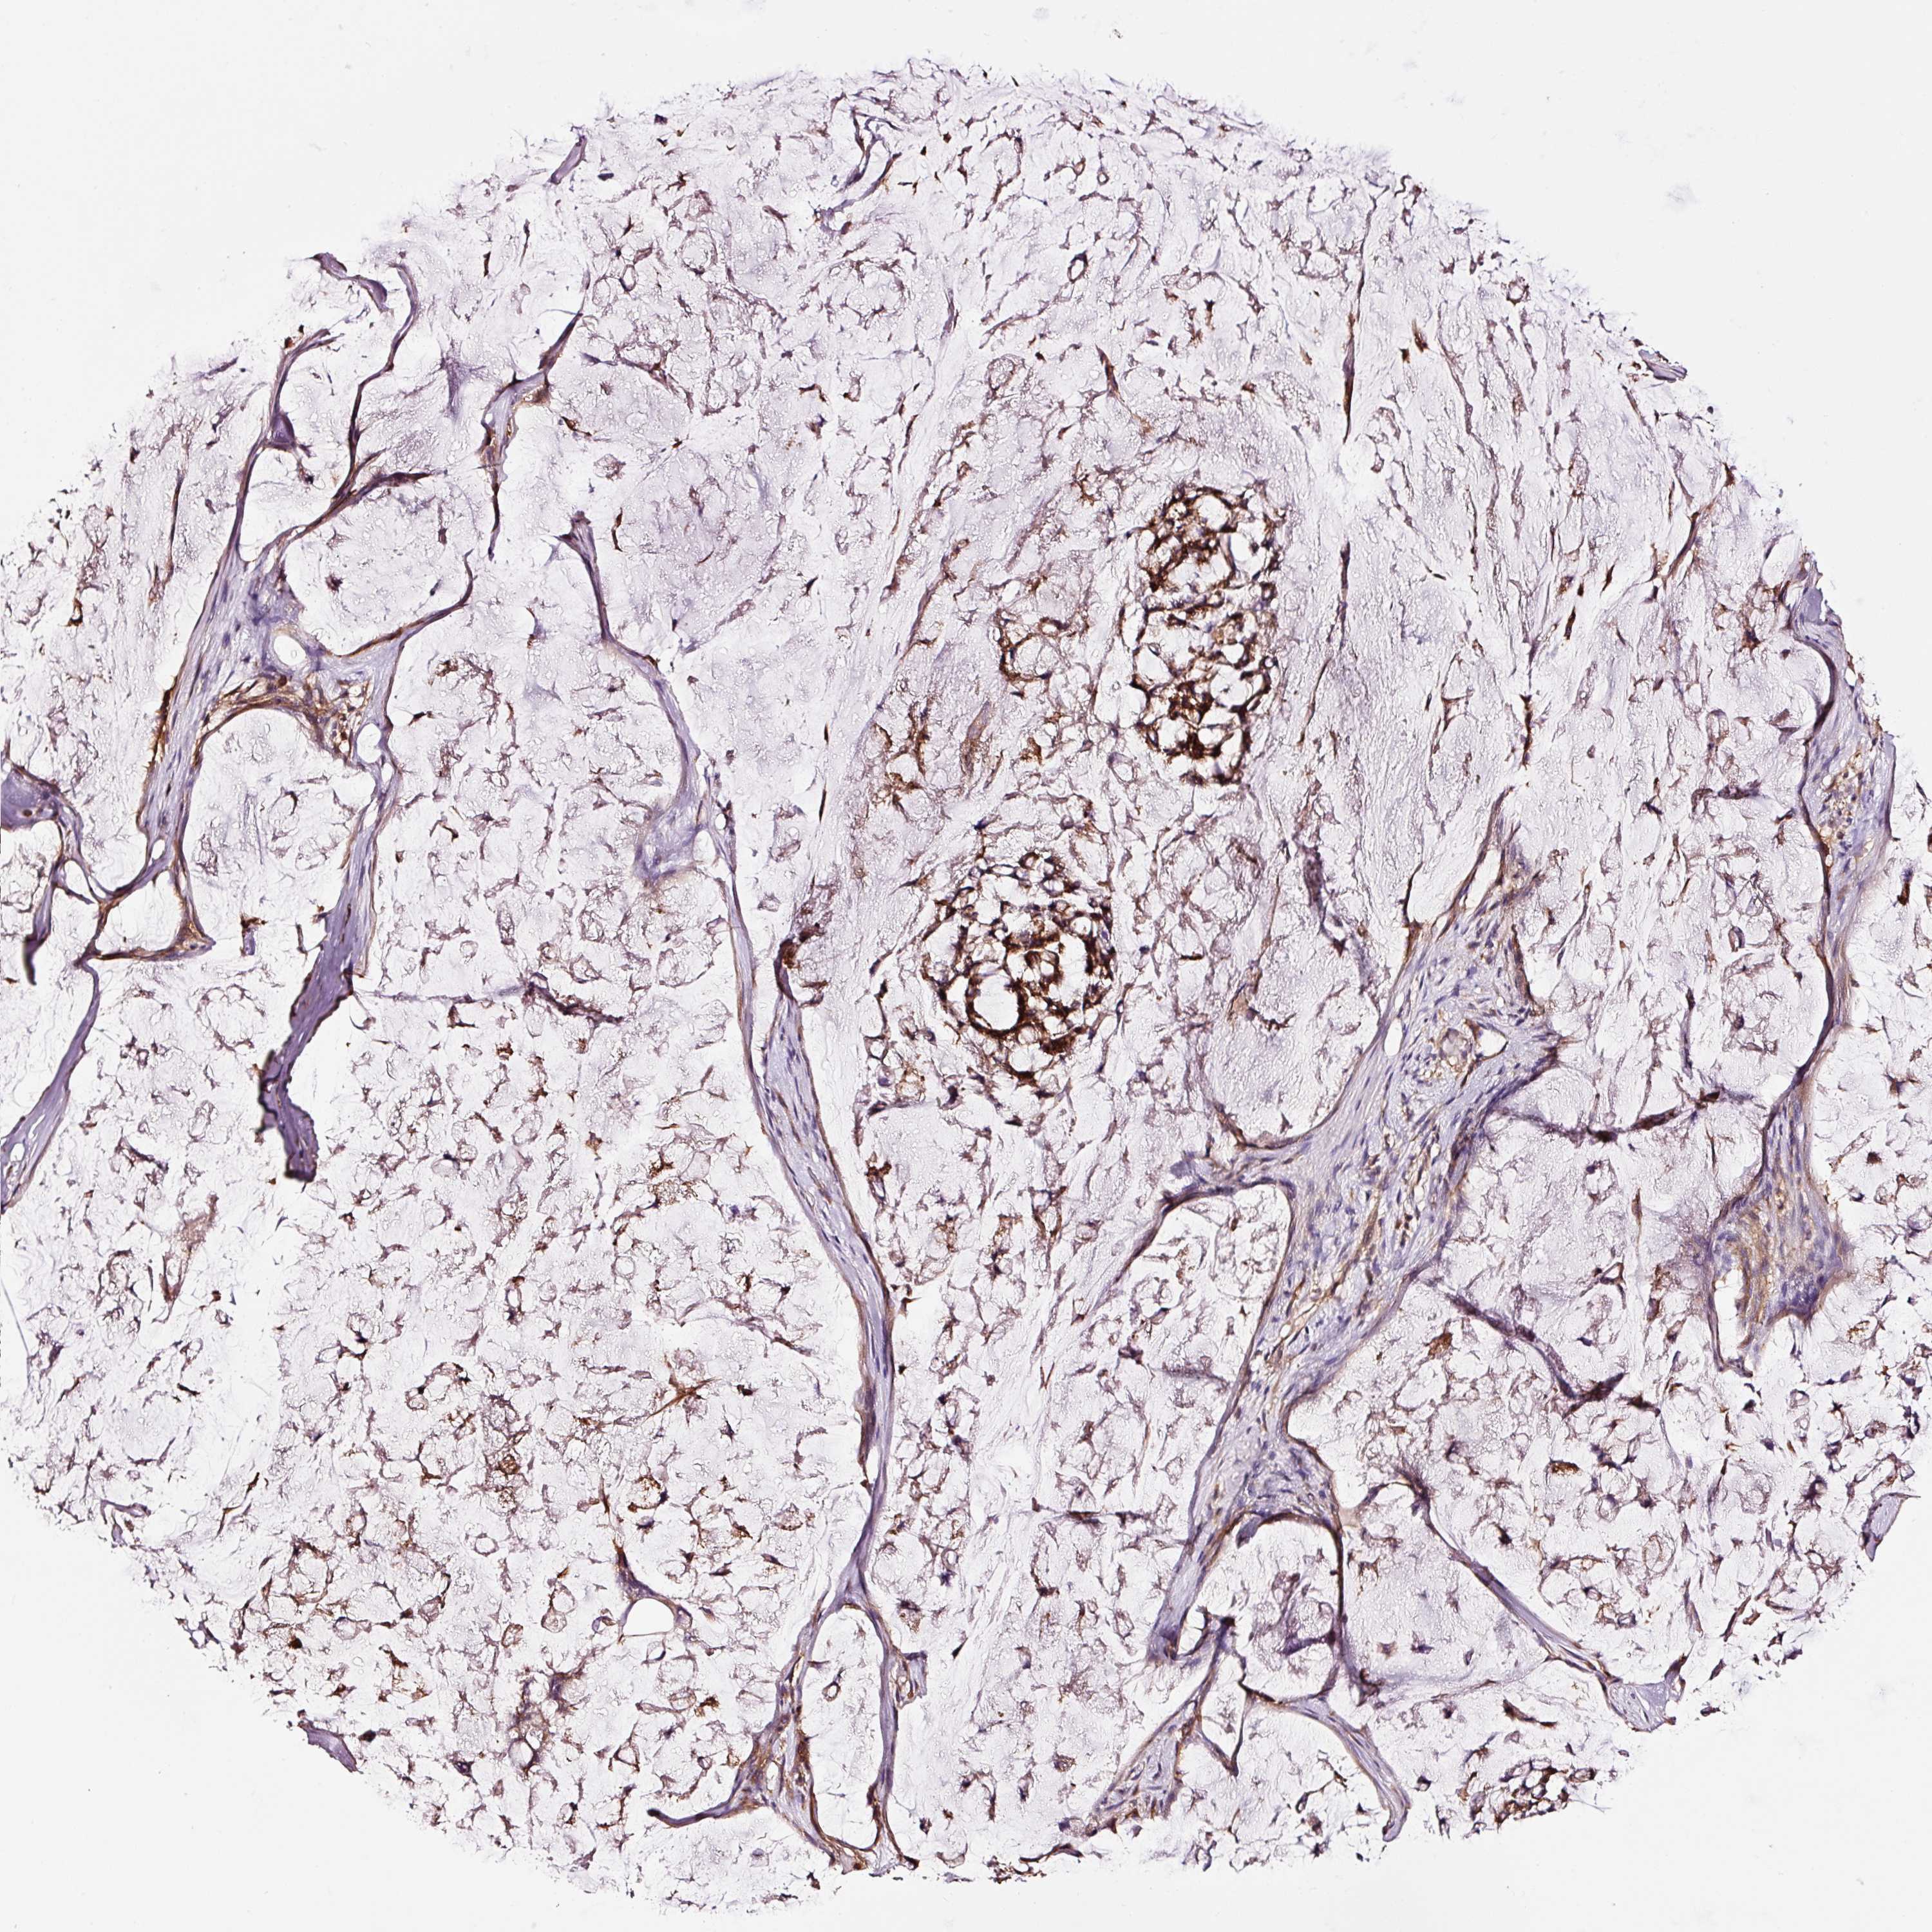

STOMACH CANCER - Protein expressioni

A mouse-over function shows sample information and annotation data. Click on an image to view it in a full screen mode. Samples can be filtered based on level of antibody staining by selecting one or several of the following categories: high, medium, low and not detected. The assay and annotation is described here.

Note that samples used for immunohistochemistry by the Human Protein Atlas do not correspond to samples in the TCGA dataset.

Antibody stainingi

Antibody staining in the annotated cell types in the current human tissue is reported as not detected, low, medium, or high, based on conventional immunohistochemistry profiling in selected tissues. This score is based on the combination of the staining intensity and fraction of stained cells.

Each image is clickable and will lead to virtual microscopy that enables deeper exploration of all samples and also displays staining intensity scores, fraction scores and subcellular localization as well as patient and tissue information for each sample.

Antibody HPA037997

Antibody HPA037998

Antibody CAB025485

Staining

Adenocarcinoma, NOS